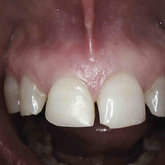

Porcelain crowns and restorations made in one appointment.

We make it a priority to incorporate the latest in dental technology in everything we do at our practice. ...